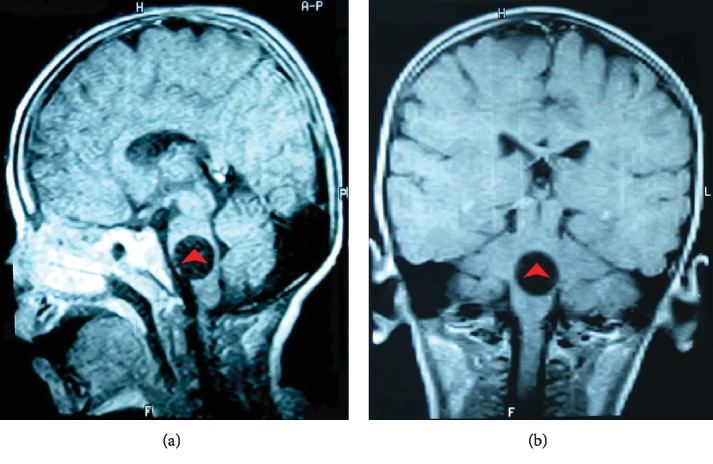

脑部核磁共振成像显示脑桥有一个轮廓分明的圆形病灶。它的测量值为21毫米,与脑脊液等强度,并且没有增强对比度。中线结构无水肿或移位(图1)。脑计算机断层扫描(CT)证实脑桥中存在明显的囊性病变(图2)。CT扫描显示肝脏有许多边界光滑的小圆形囊肿,左肾有一个小囊肿。

图1,非对比T1加权磁共振成像显示圆形,边界清楚,等信号囊肿(红色箭头)。矢状图像。冠状图像。